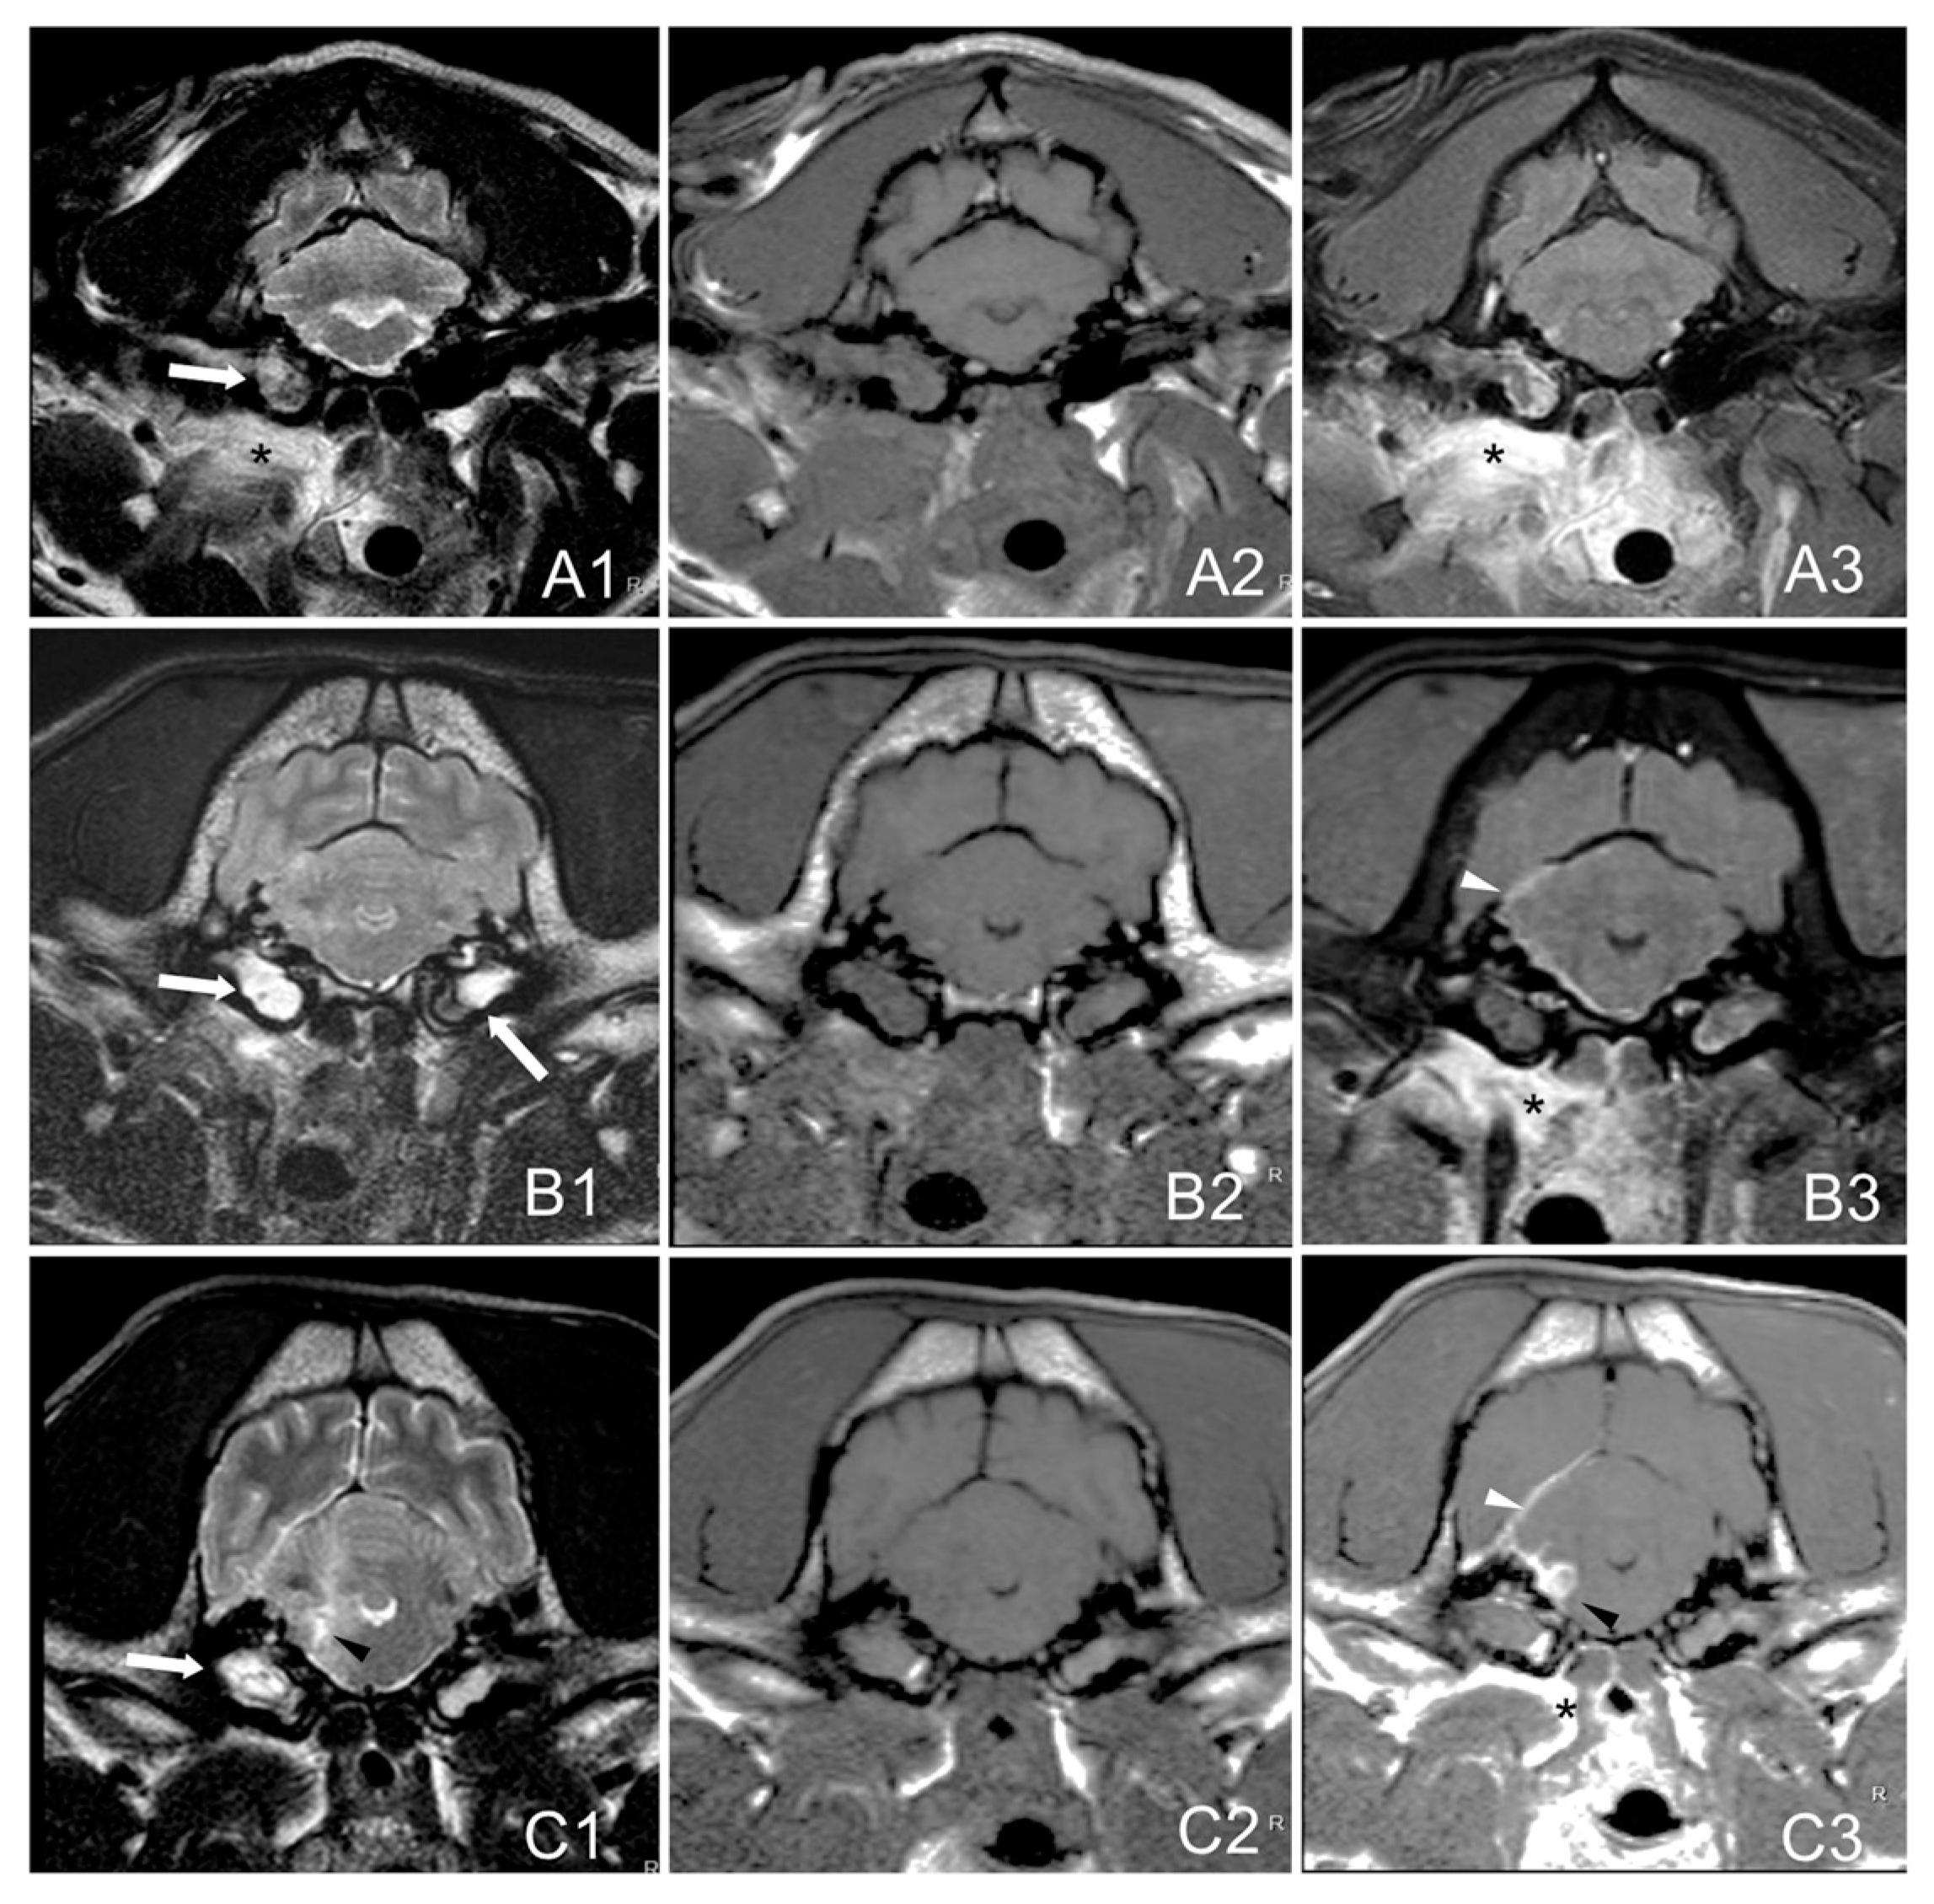

MRI images were evaluated for the presence of inflammatory changes which included: soft tissue material within one or both tympanic cavities (T2W hyperintense with T1W post-contrast enhancement), changes in para-aural soft tissues (diffuse hyperintensity in T2W and isointensity in T1W with post-contrast enhancement), meninges (T1W post-contrast enhancement), brain parenchyma (T2W hyperintensities, or suspected abscess with a T1W-hypointense, T2W-hyperintense center, and strongly-contrast enhancing rim), and the accumulation of extra-axial material corresponding to the formation of empyema (T2W-hyperintense, T1W-hypointense with peripheral contrast enhancement) [3]. The degree of contrast enhancement was described as mild, moderate, or marked, and the pattern as homogeneous or heterogeneous. The presence of nerve (facial and/or vestibulocochlear) thickening and/or enhancement was also assessed.

Group A: bulla/bullae occupation and changes in surrounding soft tissues without evidence of extension to the adjacent meninges or neuroparenchyma.

Group B: bulla/bullae occupation, changes in surrounding soft tissues and imaging of meningeal post-contrast enhancement.

Group C: bulla/bullae occupation, changes in surrounding tissues, meningeal enhancement, and brainstem lesion with or without the formation of an empyema (Figure 1).

Figure 1. Magnetic resonance images (MRIs) of the head on a transverse plane at the level of the tympanic bullae of three dogs with otitis inter-media showing the proposal MRI grading system. T2W: (A1,B1,C1). T1W: (A2,B2,C2). Post-contrast-T1W: (A3,B3,C3). Group A. French bulldog, 4 years (A1A3): bulla occupation (white arrow) and changes in surrounding soft tissues (asterisk) without apparent radiological encephalon extension. Group B. French bulldog, 7 years (B1B3): bullae occupation (white arrows), changes in surrounding soft tissues (asterisk) and imaging of meningeal enhancement (white arrowhead). Group C. French bulldog, 9 years (C1C3): bullae occupation (white arrows), changes in surrounding tissues (asterisk), meningeal thickening (white arrowhead), and brainstem space-occupying accumulation of epidural material corresponding to the formation of an abscess or empyema T2W-hyperintense with peripheral heterogenous contrast enhancement (black arrowheads).